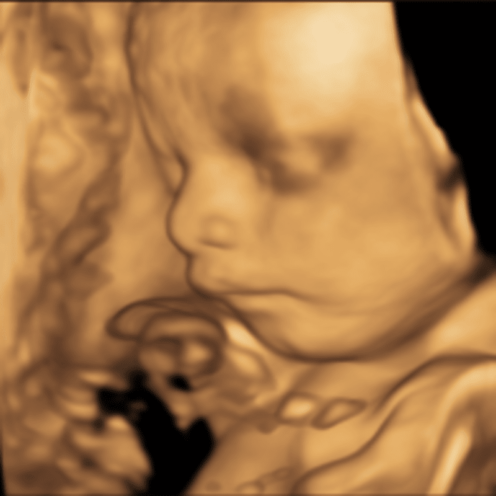

Thankyou Lauren at Chequers Health Group for getting me in each time I have needed a baby scan. You guys have been amazing, couldn't recommend enough.